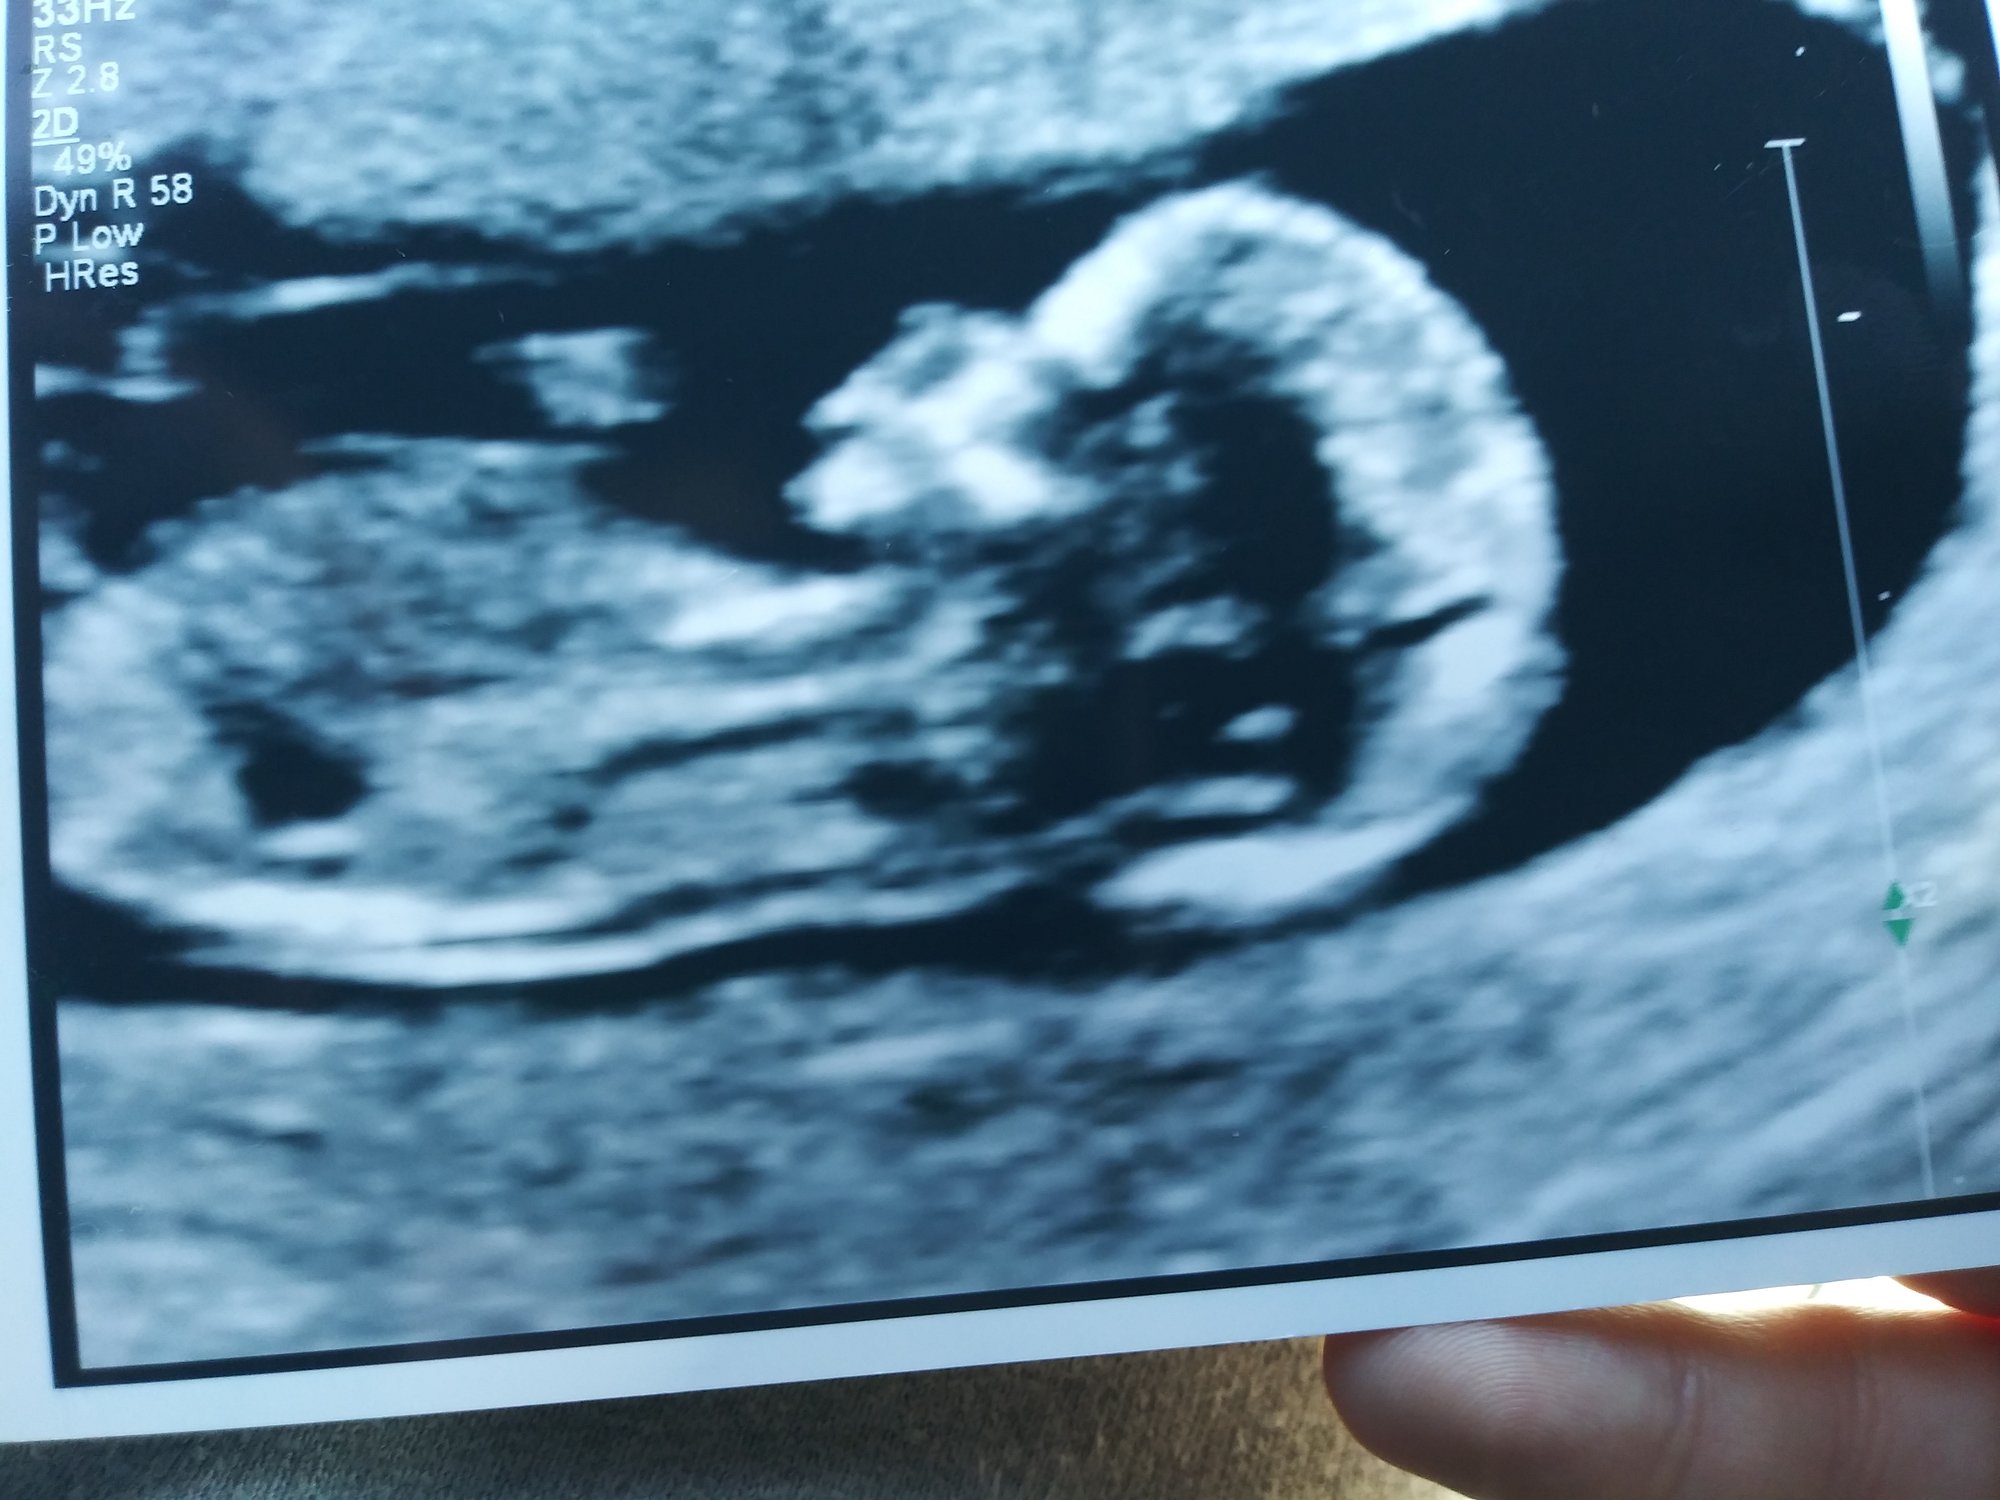

So i know this isnt the ultrasound thread but still gonna post here.

Had my NT scan today. There was a heartbeat! Doctor eventually reviewed the scans and left in my patient portal that everything looked good and normal!

So relieved.

@psychobutthead baby looks great and I totally understand why you didn't post on that thread. I was going to as well since I had a great scan Thursday and got to see baby but it just didn't seem right.

Ultrasound tech took a nub theory guess and said boy but we have a gender scan on 3/5 so we'll be sure then.